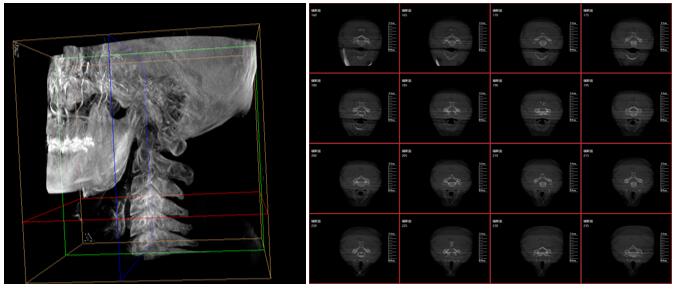

PLX7500三維成像圖片

這款新型三維C型臂—PLX7500集成手術導航和手術機器人接口,可無線傳輸三維重建的圖像數據至導航設備,無需額外手動注冊步驟,實現術中圖像的實時引導規劃,輔助醫生精準定位手術器械和植入物,為實現手術室的數字化和智能化拓展提供可能。

采用30cmx30cm的動態平板探測器,輸出高分辨率、大尺寸的二維、三維圖像。超高16比特灰階度,高動態范圍清晰顯示植入物的位置和輪廓。

強大的圖像后處理功能軟件,自動調整比較好的圖像窗寬窗位,顯著降低螺釘的金屬偽影,降低圖像區域噪點,進一步優化圖像品質。